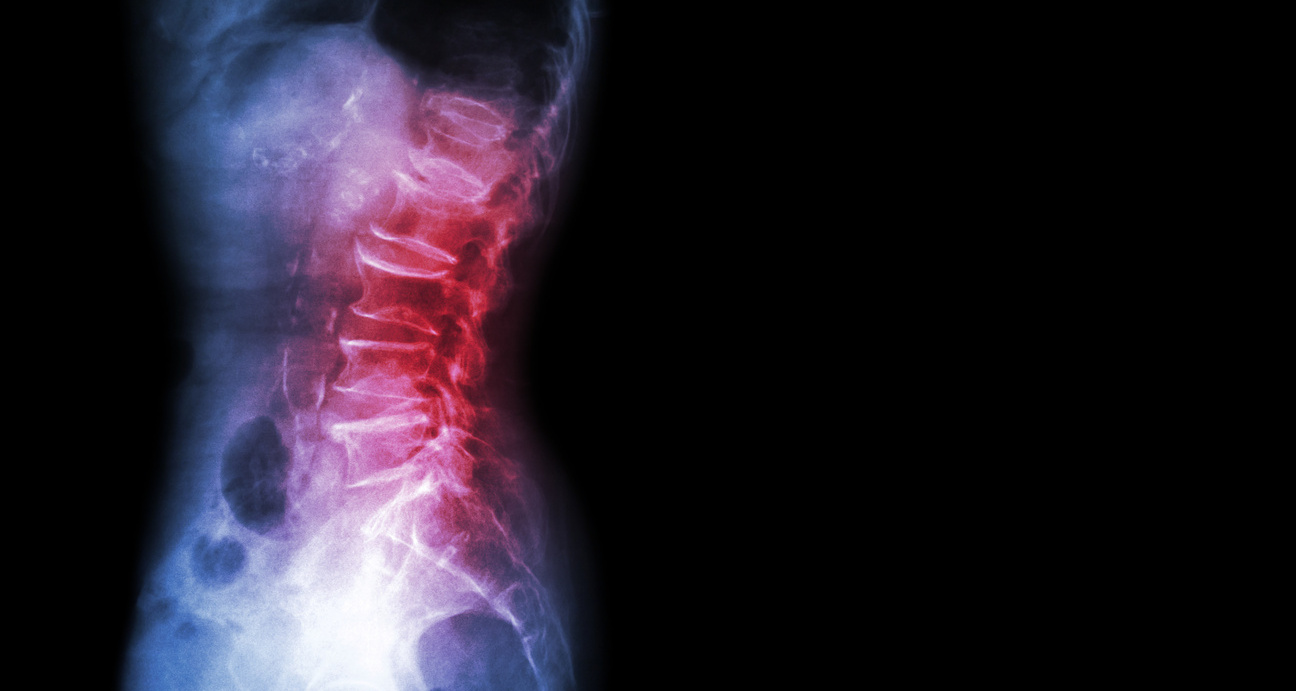

About 50 million Americans suffer from chronic pain, which interferes with their daily life, social interactions, and ability to work, reports MIT News. MIT Professor Fan Wang wants to develop new ways to help relieve that pain, by studying and potentially modifying the brain’s own pain control mechanisms.

Her recent work has identified an “off switch” for pain, located in the brain’s amygdala. She hopes that finding ways to control this switch could lead to new treatments for chronic pain.

In a study of mice treated with anesthesia drugs, Wang discovered that the brain does have this kind of switch, in an unexpected location: the amygdala, which is involved in regulating emotion. She showed that this cluster of neurons can turn off pain when activated, and when it is suppressed, mice become highly sensitive to ordinary gentle touch.